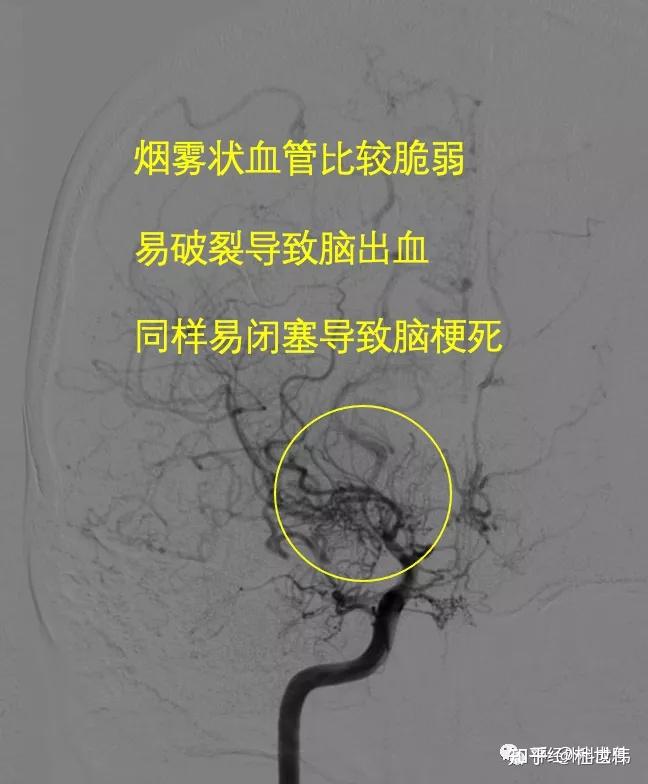

脑袋里冒烟的脑血管病烟雾病

图片尺寸648x784